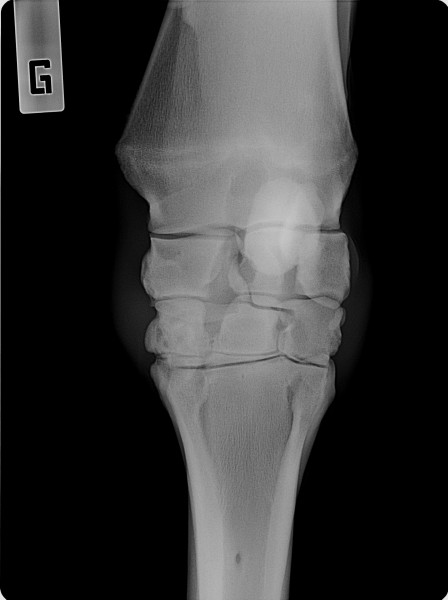

Это кто вам сказал? Если, конечно, рентгену сто лет, то наверное, а на современных машинах видны все прожилки, рельеф, сухожилия и связки как на картинке

Врач, умеющий читать снимки всё увидит.

Вот картинка для иллюстрации. Здесь должно быть виднее. (надеюсь, владелец снимка не против будет, есличе уберу)

Оба сгибателя и межкостник хорошо видны.